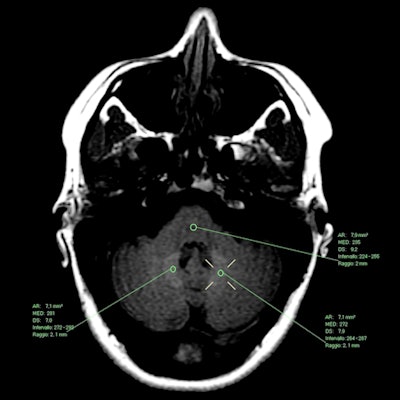

"The results of our study provide clear evidence that T1 signal changes can and do occur in the dentate nucleus after multiple administrations of the macrocyclic GBCAs gadobutrol and gadoterate meglumine, and that the appearance of visible T1 hyperintensity is associated with significant increases in dentate nucleus/pons signal intensity ratio," wrote lead author Dr. Alessandra Splendiani and colleagues at the University of L'Aquila.

In comparing T1 hyperintensity before and after MRI scans, 42 patients (28%) showed statistically significant differences in mean dentate nucleus/pons signal intensity ratio for the individual GBCAs and when patients received both contrast agents.

Mean dentate nucleus/pons signal intensity ratios in patients with T1 hyperintensity | ||||

No. of patients | Before 1st scan | Before last exam | p-value* | |

Gadobutrol | 19 | 0.998 | 1.153 | < 0.0001 |

Gadoterate | 15 | 1.003 | 1.110 | < 0.0001 |

Both GBCAs | 8 | 1.004 | 1.163 | < 0.0004 |

Total | 42 | 1.003 | 1.137 | < 0.0001 |

"Typically, the first appearance of visible T1 hyperintensity in positive patients occurred at the fourth or fifth follow-up exam, [and] between approximately three and four years after the initial MRI examination," the authors wrote.